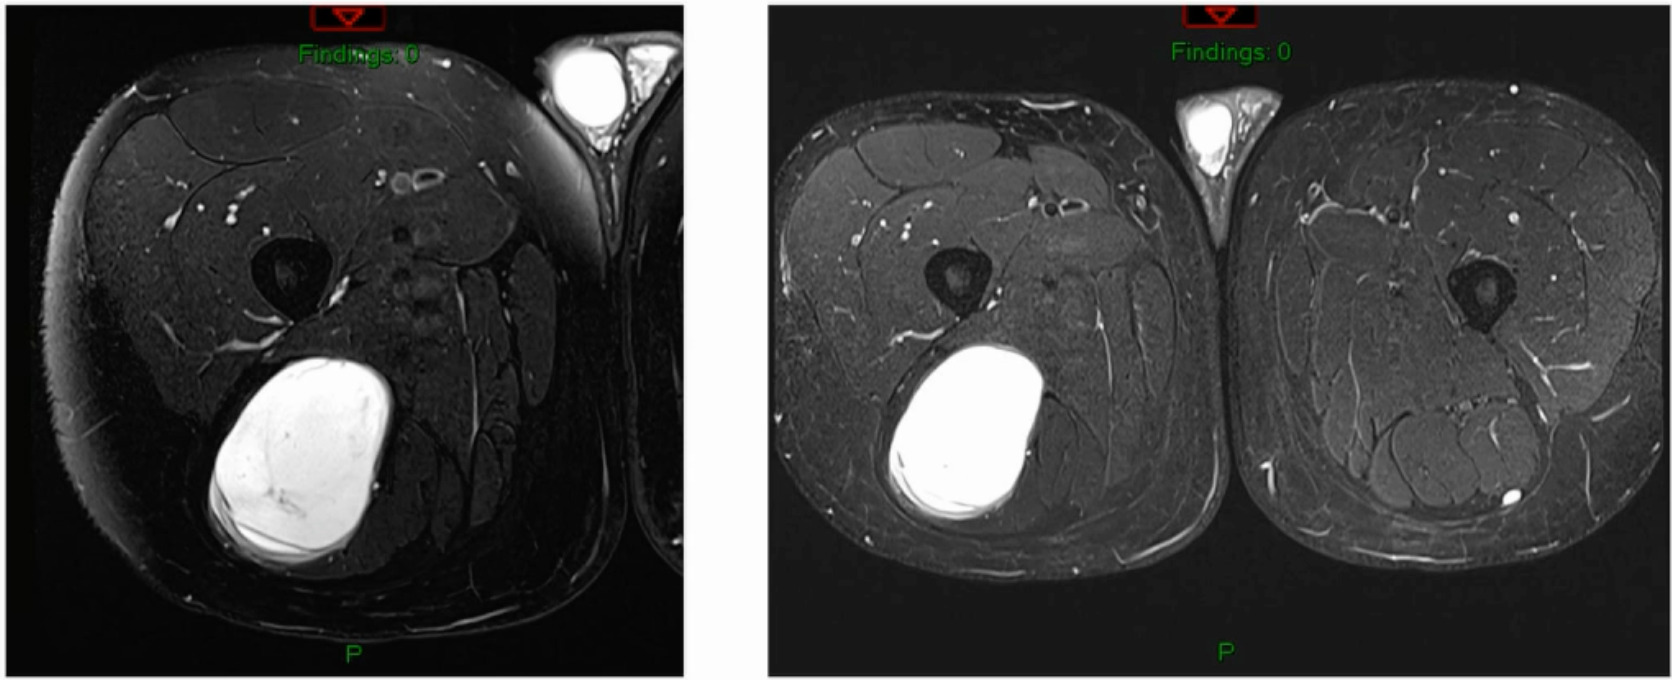

This is a 76-year-old that I just saw this week that had a bump on her thigh annd this is the report (Figure 4).

Unsure what it is? Intramuscular lipoma? Intramuscular lipomas aren’t firm and they aren’t hot. Ultrasound for that? The “gold standard” would be an MRI, not an ultrasound, but they did ultrasound it. The ultrasound came back with, “should get an MRI.” But they biopsied it instead. An MRI was then obtained after the biopsy. (Figure 5)

The biopsy came back as a myxoid fibrosarcoma they biopsied it with a needle, so it’s very hard to tell grade. Additionally, if I’ve got a tumor that’s this big and I’ve got a needle the size of a pin then my sampling error is massive. I don’t ever believe grade off of a biopsy. I just get biopsies so that now I can at least give radiation or do whatever pre-operatively. She is starting her radiation next week for a number of reasons. But she’s got a myxoid fibrosarcoma.